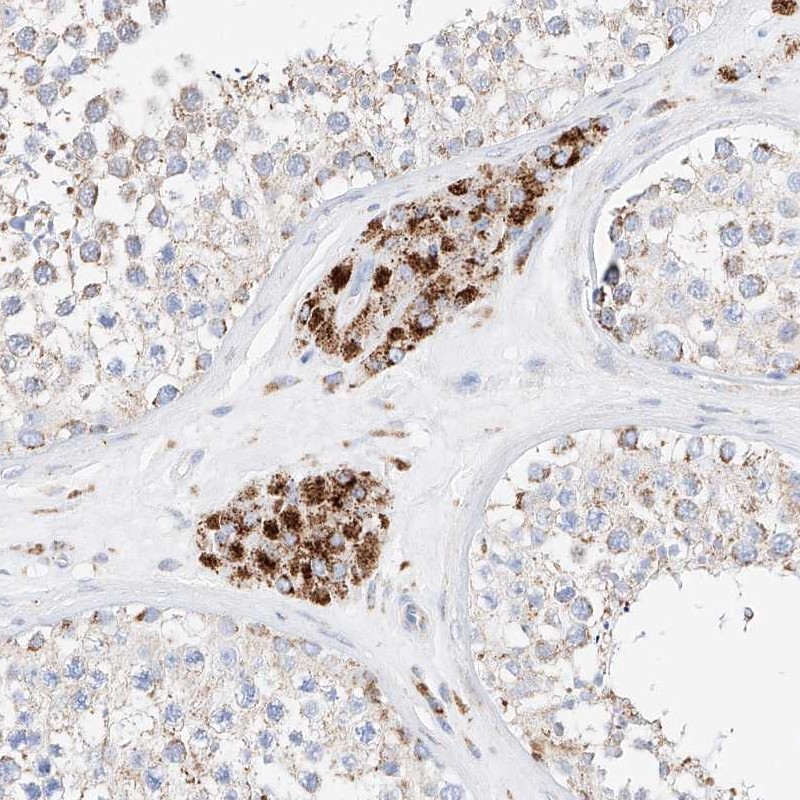

Immunohistochemistry analysis in human testis and pancreas tissues using Anti-C6orf62 antibody. Corresponding C6orf62 RNA-seq data are presented for the same tissues.